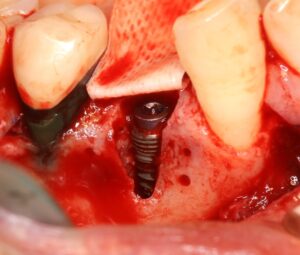

今回の症例では、インプラント埋入直後はネジ山の大部分が露出した状態でしたが、同時に骨造成手術を行ったことで、6か月後の2次手術時には良好な骨再生を確認できました。

インプラント埋入直後